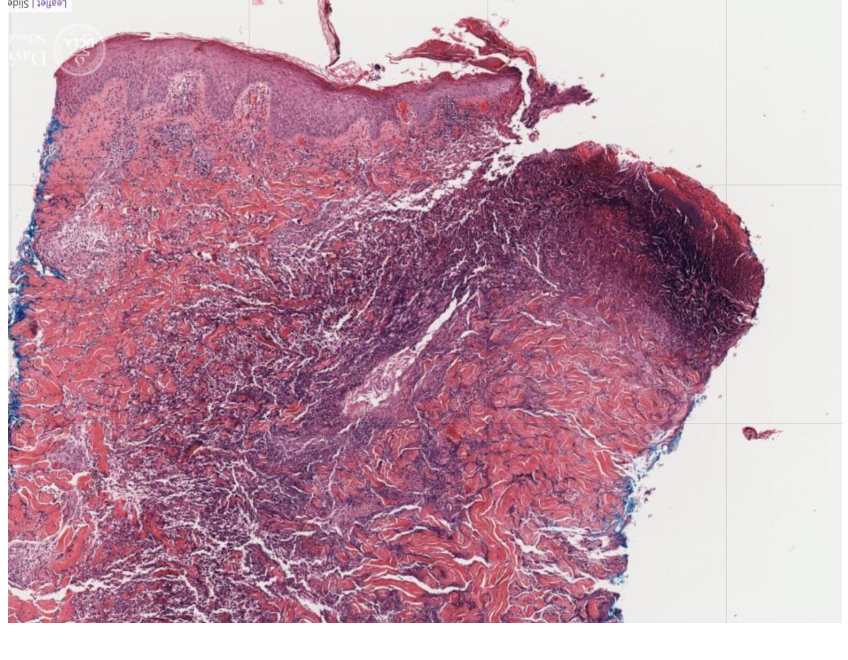

Is the dermal/epidermal junction intact?

NO! Full thickness loss of epidermis, definition of an ulcer